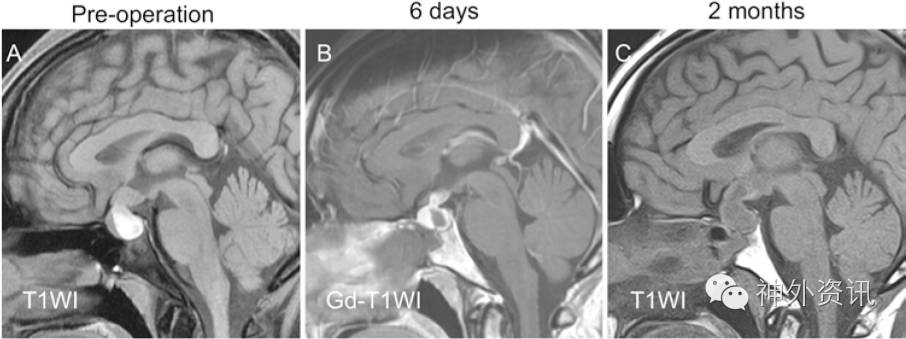

图2. 1例慢性头痛和闭经起病的32岁女性患者MRI图像:A.术前MRI-T1相显示鞍内、鞍上的等信号至高信号囊肿;B.术后第6天MRI-T1增强相显示囊肿消失;C.术后2个月发现囊肿复发。